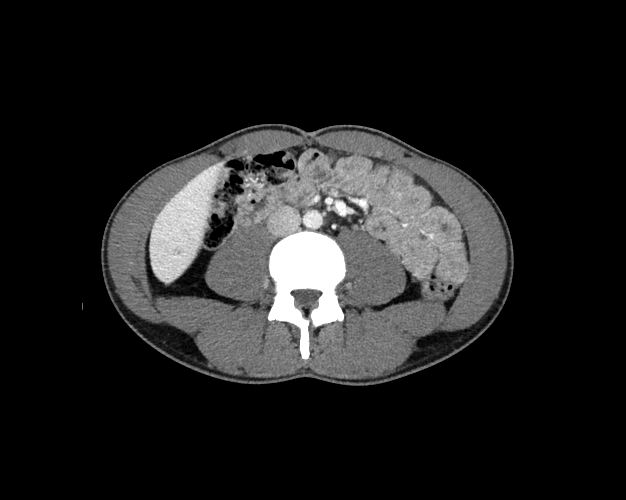

Body

Covers abdominal CT anatomy.